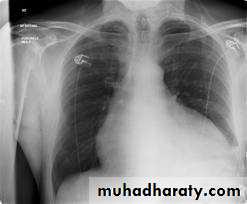

CXR – ECHO

CXR: Useful if there is effusionECHO :can detect even small amount

Ecg + CXR + ECHO

-CXR-Increase cardiac sillhoutte

Flask shaped enlargement

-CXR- cardiomegaly